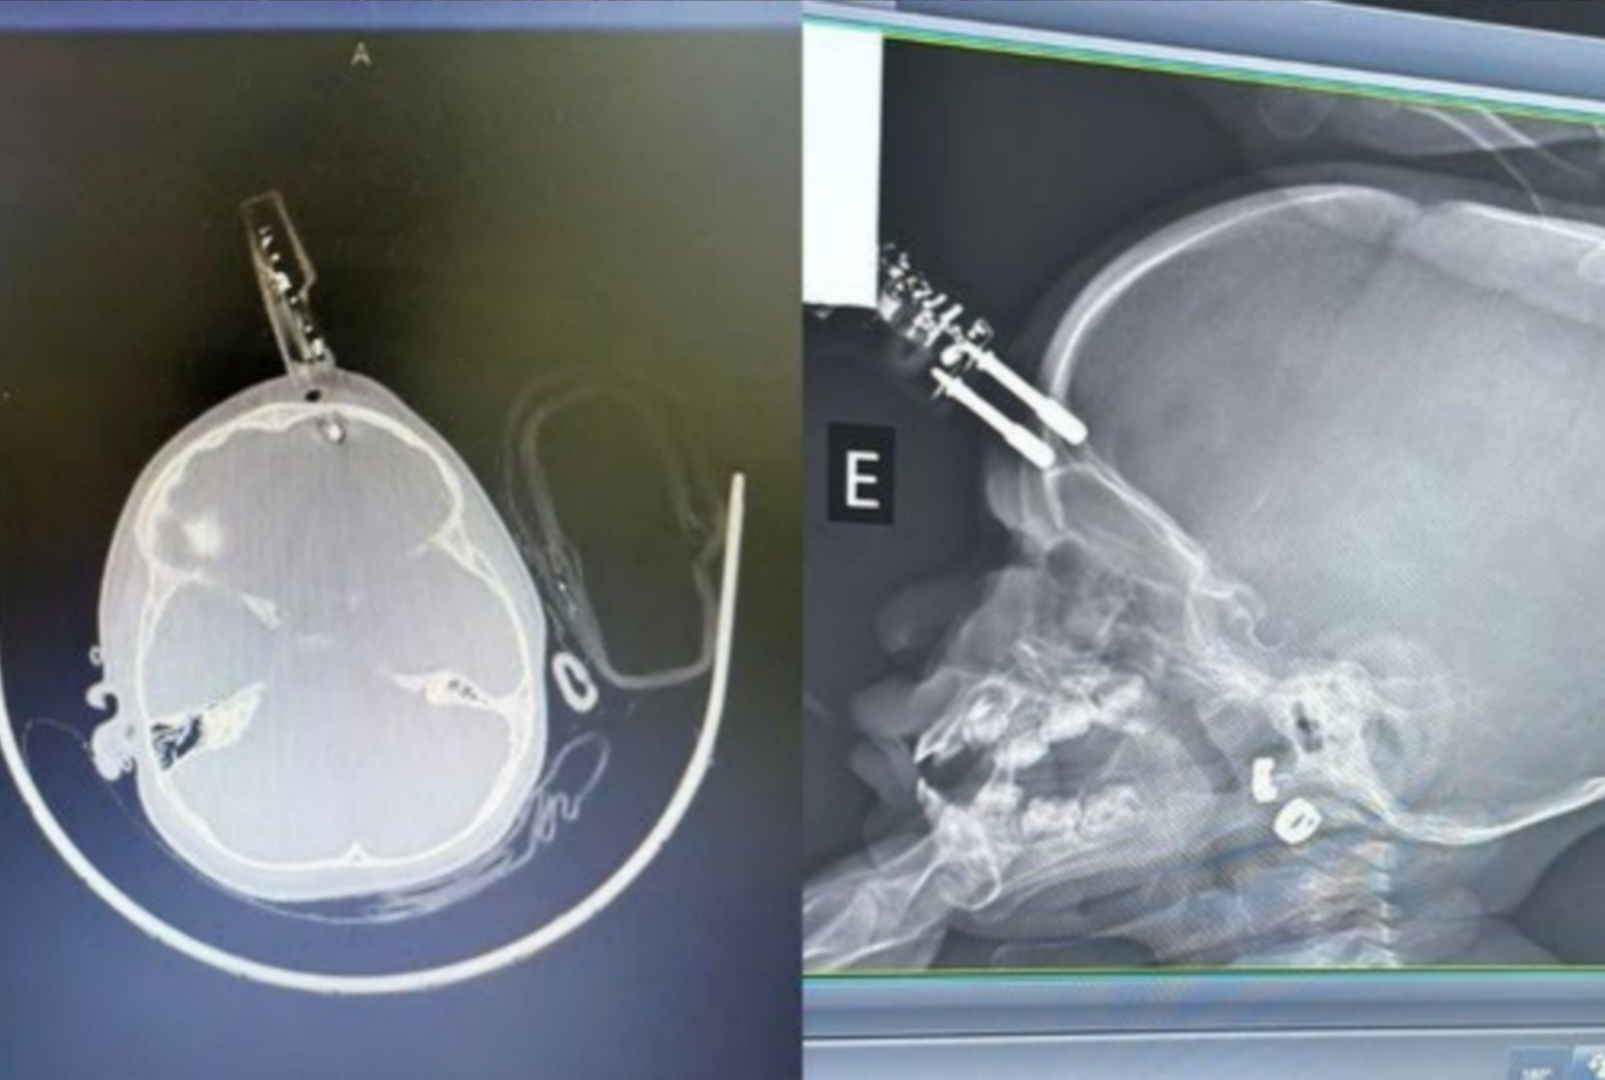

O acidente ocorreu na última terça-feira, dia 13, e mobilizou rapidamente equipes médicas devido à gravidade da lesão. Segundo informações médicas, o impacto fez com que um dos pinos do carregador perfurasse o osso frontal do crânio, próximo à região dos olhos, alcançando o cérebro. A principal hipótese é que a menina estivesse com o objeto nas mãos no momento da queda, o que transformou um acidente comum em uma situação de alto risco.

A mãe da criança teria se ausentado por alguns instantes para ir ao banheiro quando a queda aconteceu. Ao retornar, encontrou a filha chorando e com sangramento, acionando imediatamente o socorro. A menina foi levada com urgência ao hospital, onde passou por exames de imagem que confirmaram a perfuração craniana e a necessidade de cirurgia imediata.

O procedimento foi conduzido pelo neurocirurgião Bruno Castro e envolveu a retirada cuidadosa do carregador, limpeza profunda da área atingida, lavagem para reduzir o risco de infecção, fechamento da lesão e reconstrução da região afetada. A rapidez no atendimento foi considerada fundamental para evitar complicações mais graves, como hemorragias intracranianas, infecções severas ou danos neurológicos permanentes.